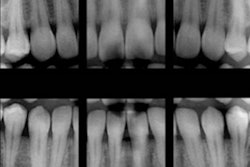

Image courtesy of the Alliance for Radiation Safety in Pediatric Imaging.This is the message that the new Image Gently in Dentistry campaign will launch this September. The campaign is supported by the Alliance for Radiation Safety in Pediatric Imaging, a coalition of healthcare organizations dedicated to providing safe, high-quality pediatric imaging worldwide. The primary objective of the alliance is to raise awareness in the imaging community of the need to adjust radiation dose when imaging children.

Use the fastest image receptor available. When film is used for intraoral radiography, it should be F-speed. When digital imaging is applied, the exposure parameters should be set as low as diagnostically necessary.